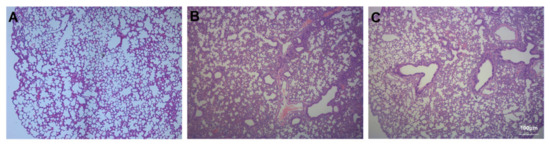

3.2. Assessment of Lung Injury and Neutrophil Infiltration

3.3. Assessment of Pulmonary Fibrosis